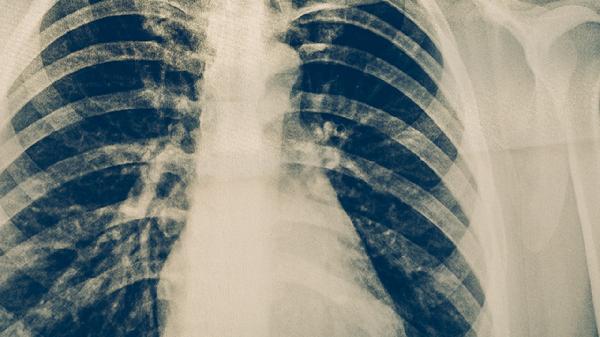

2、复查影像学

需立即进行胸部CT检查明确肺部病灶变化,若发现活动性结核病灶需重新评估痰菌情况。胸片联合B超可判断是否存在胸腔积液,CT增强扫描能鉴别胸膜增厚与肿瘤复发。影像复查频率应根据疼痛程度调整为1-2周一次。